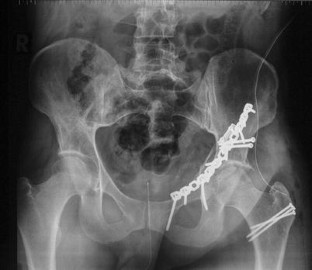

Vordere Pfeilerfraktur des Acetabulums mit dorsaler Impression

Anterior column fracture of the acetabulum with dorsal impression

Es wird ein ungewöhnlicher Fall einer vorderen Pfeilerfraktur des Acetabulums mit ausgedehnter Impression im Bereich des hinteren Pfeilers beschrieben. Nach primärer Osteosynthese über einen ilioinguinalen Zugang erfolgt die Reposition der dorsalen Impressionen über einen hinteren Zugang mit Repositionskontrolle mittels chirurgischer Hütluxation.

An unusual case of an anterior column fracture of the acetabulum with extended marginal impaction at the posterior column is presented. Fracture fixation was primarily performed by an ilioinguinal approach followed by a posterior approach with surgical dislocation of the hip to reduce the impacted fragments.